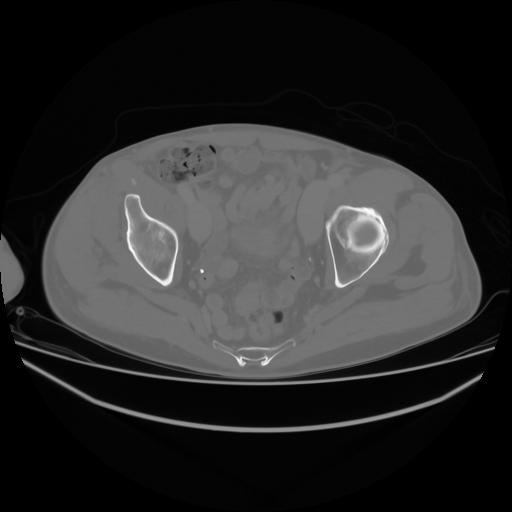

4 CUERPO,CE,Axial,3.0,CUERPO,,